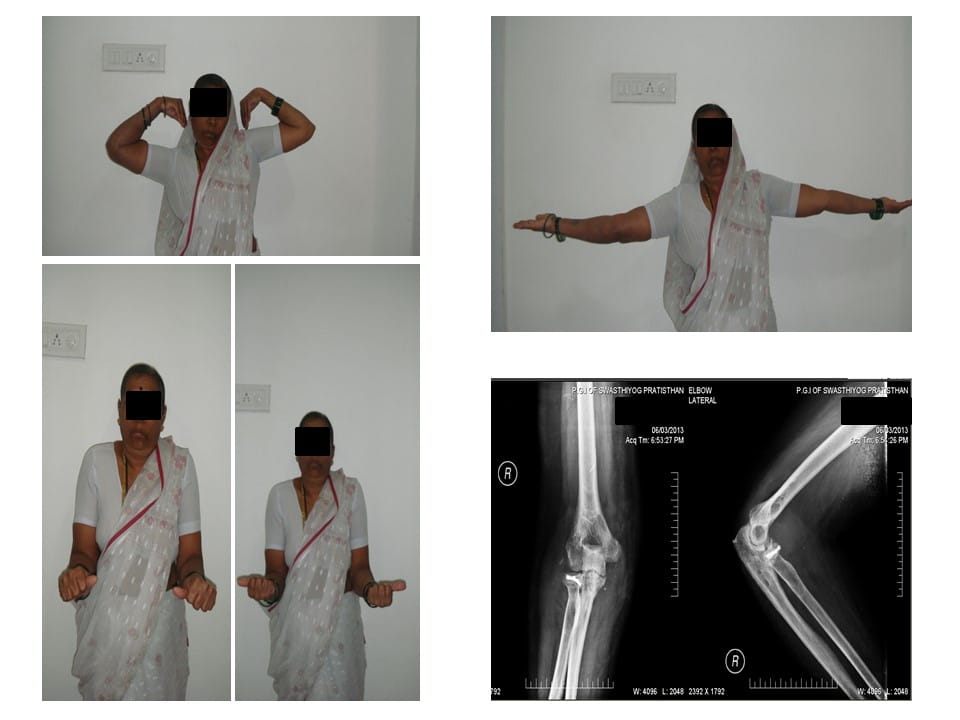

Terrible Triad